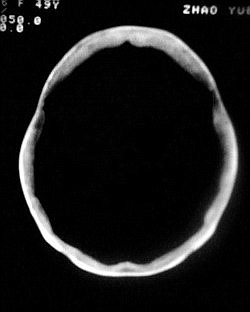

3、“钙化点”是指哪一个呀?是四叠体池左旁的那个吗?那个不好说,可能是感染性病变留下的,我估计临床意义不大,实在不放心做个增强看看有没有其它什么东东。

1.颅骨对称性、形态规整性增厚,应属发育异常。四叠体池左后侧单发点状钙化,无其他阳性表现,多属正常,不需要过多关注。

2.双侧基底节区域多发性梗塞灶。

1.双侧基底节区腔梗。

2.颅骨内外板广泛性增厚,板障狭窄甚至消失,双侧对称。无明显相应临床症状。考虑“泛发性骨皮质增厚症”。可进一步检查下颌骨及管状骨骨干。(下颌骨骨小梁增多、密集,密度增高亦为本病特点,管状骨骨干皮质向内增厚引起骨皮质厚度增加,骨密度增浓、髓腔狭窄但不消失,骨干周径较少增加)。与石骨症鉴别,后者很少影响颅盖骨和下颌骨,管状骨改变主要累及干骺端和骨骺,而骨干皮质较少增厚,椎体和髂骨翼有特征性表现。